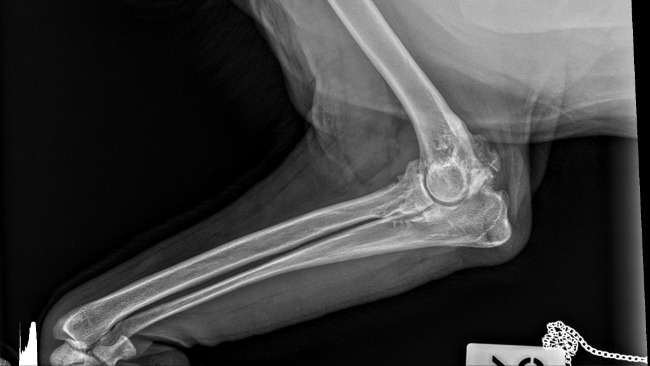

Nóżka Kokoszka, choć nadal obrzęknięta, dobrze się goi i nasz dzielny psiak stawia na niej swoje wielkie łapeczki.

Fot. Droga chłopaków do równowagi psychicznej. Wizyty w gabinecie lek.wet.

Małgorzata Płoskonka